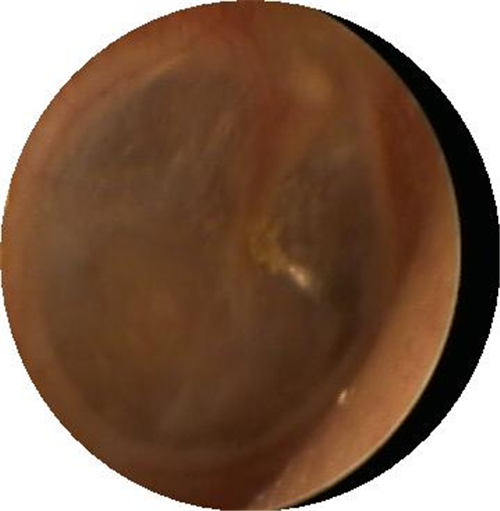

鼓膜穿孔圖片

左耳鼓膜穿孔